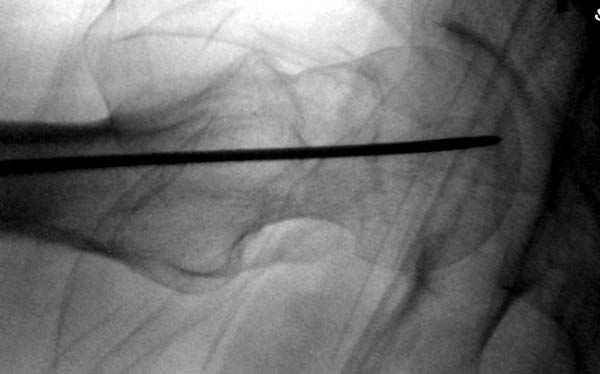

На второй день после выписки упал дома. Снимки приложены. Коллеги рекомендуют удаление шурупа и вытяжение. Что делать?

Привет из солнечного Будапешта с Eurotrauma-2008. Да, замечательный пример. Получается, профилактику расхождения отломков шейки надо было проводить каким-то реконструкционным или проксимальным гвоздем, причем сразу длинной версией. Сейчас, наверно, так и надо бы сделать.

Убрать винты, каким-то джойстиком в вертельной области сделать репозицию шейки, фиксировать ее спицами, а дальше вправлять и фиксировать как вертельный перелом.

Правильно, ситуация изменилась, как говорят у нас теперь "different animal", надо решать проблему подвертельного перелома. При наличии различных вариантов фиксаторов, включая Страйкер Гамма 3, мы выбрали DePuy Antegrade Trachanteric Nail из-за многовариантности проксимальной фиксации и двойного изгиба. Вводится через вертел под 8 градусным углом, и есть достаточный передний диафизарный изгиб, предупреждающий пенетрацию дистального переднего кортекса.